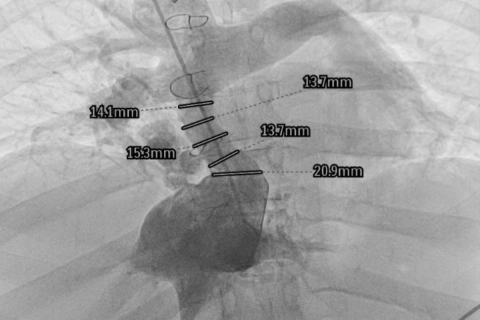

U pacjentki wszczepiony chirurgicznie konduit (przewód) doprowadzający krew z żyły głównej dolnej do łożyska płucnego uległ istotnemu zwężeniu. Kardiolodzy interwencyjni z dostępu przez żyłę główną górną (obie żyły udowe były niedrożne) poszerzyli ten konduit stentgraftem z bardzo dobrym efektem.